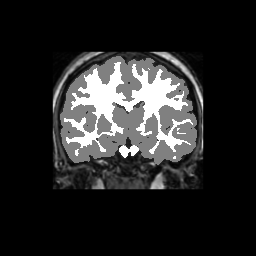

Accuracy is reported as Dice overlaps between a tool's segmentation and the Internet Brain Segmentation Repository (IBSR) manual segmentation for each of the 18 IBSR subjects. The inter-tool comparison (on the left below) shows the median Dice coefficient for each tissue class. The overlaps for FSL (from which the median values are drawn) are shown in the plot on the right.

Subject Accuracy (IBSR)

Overlap coefficients for each tissue class are shown here for each IBSR subject. Select a subject below to see the FSL results compared to other tools.